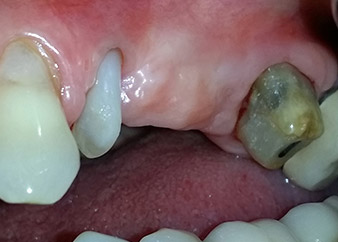

Une patiente de 58 ans se plaignait de douleurs et d'une mobilité accrue de la dent pilier 24 de son bridge. Présence d'une inflammation parodontale avec formation de poches de 7 mm de profondeur dans le sens mésiobuccal et de plus de 12 mm dans le sens distal, ainsi que d'une atteinte de la furcation au troisième degré. La radiographie a par ailleurs révélé une lésion parodontale étendue autour de la région apicale de la dent 24 ayant préalablement reçu un traitement endodontique (alio loco) (Fig. 1).

Un an plus tôt, les dents 25 et 26 avaient été extraites à la suite d'un traumatisme et pour cause d'atteinte endo-parodontale, avant la pose du bridge. Une lésion endo-parodontale combinée a été diagnostiquée pour la dent 24, d'étiologie incertaine. La patiente voulait conserver ses dents piliers 24 et 27 et refusait toute prothèse amovible à titre définitif, et même provisoire. Par conséquent, malgré un pronostic défavorable compte tenu des résultats des radios et des examens cliniques, il a été convenu de faire le maximum pour conserver les deux dents.

Un mois plus tard, le jour de l'intervention, la douleur et l'inflammation sur la dent 24 étaient minimes mais une mobilité de classe 2 de Miller était toujours observable. Après ouverture des lambeaux et nettoyage des tissus périapicaux et périradiculaires infectés, l'étendue du défaut osseux est devenue parfaitement visible (Figures 2 et 3).

À la racine de la dent, il manquait la totalité de l'os vestibulaire et distal. L'attache était essentiellement limitée à la racine palatine, venant ainsi confirmer le pronostic défavorable initial. La dent 27 présentait également une attache horizontale réduite et une raréfaction apicale minime (cf. Fig. 1), sans symptômes cliniques.